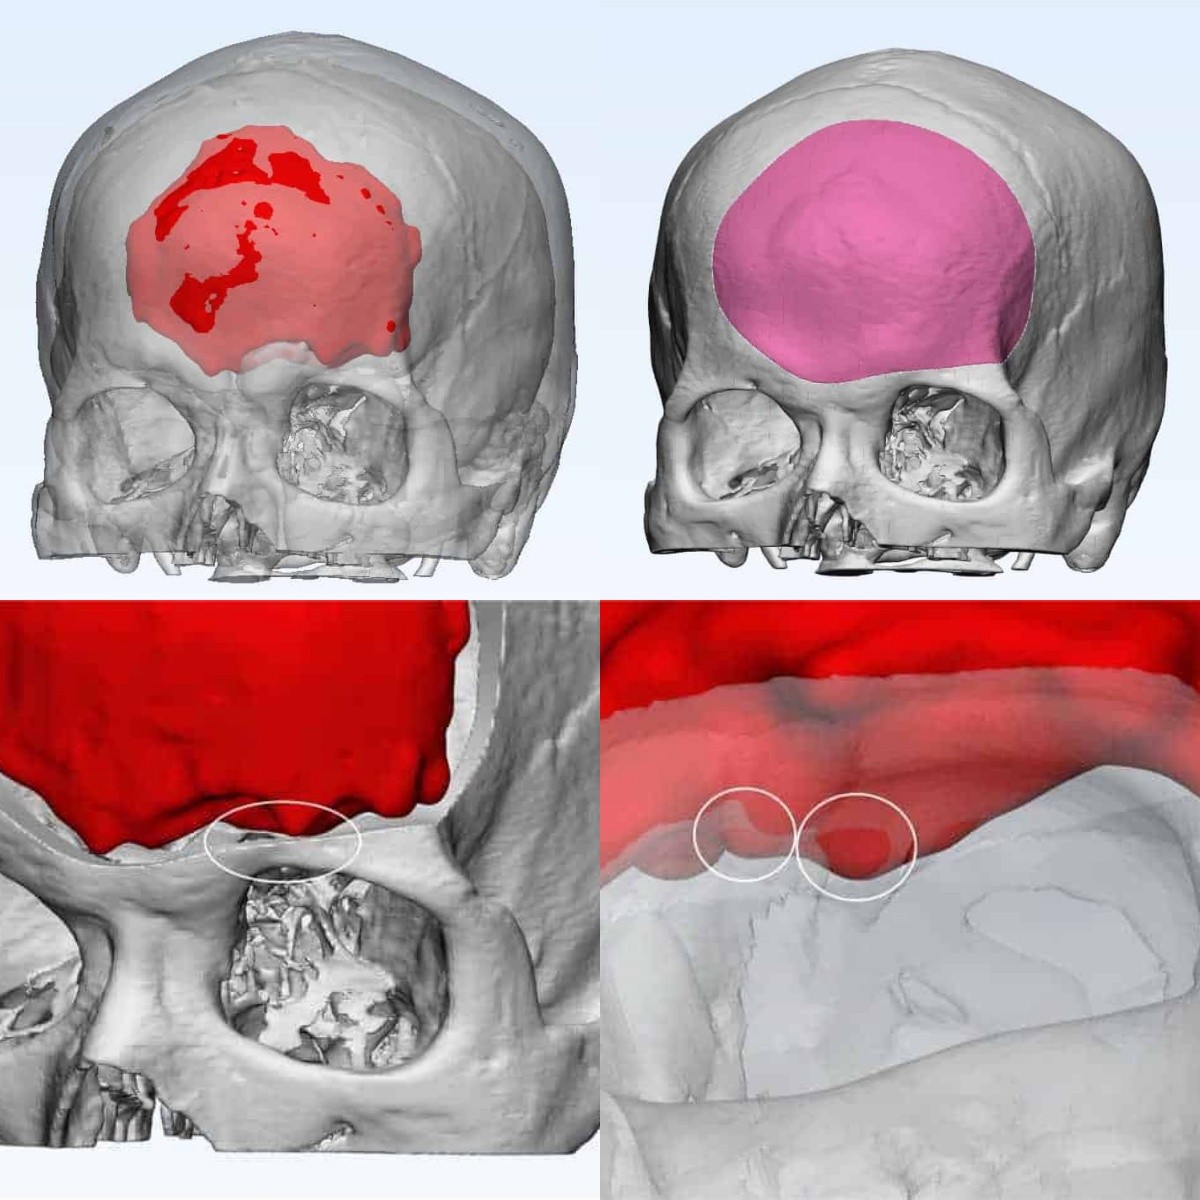

影像重建

腫瘤與靜脈、矢狀竇的關系

靜脈影像重建

CT重建

左額內外板可見骨質增生